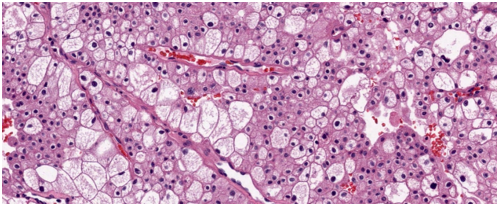

Vi thể

Thường gặp các đám và bè tế bào sắp xếp chặt chẽ, tế bào có bào tương sáng và màng tế bào rõ. Bào tương hạt bắt màu eosin có thể được quan sát trong các khối u độ mô học cao hoặc ở vùng lân cận các ổ xuất huyết hay hoại tử. Hệ thống các mạch máu nhỏ, thành mỏng,phân nhánh dạng cây là một đặc điểm chẩn đoán quan trọng, đặc biệt trong các trường hợp có bào tương hạt eosin. Các kiểu cấu trúc kiến trúc gồm dạng đặc, dạng phế nang hay dạng ổ (alveolar hoặc nested), dạng tuyến nang hay ống (acinar hoặc tubular), dạng vi nang chứa hồng cầu thoát mạch hoặc dịch ái toan, và đôi khi dạng đại nang. Có thể gặp cấu trúc nhú khu trú, tuy nhiên sự hình thành nhú nổi bật làm tăng khả năng các phân nhóm khác như u thận tế bào sáng dạng nhú, ung thư biểu mô tế bào thận có tái sắp xếp TFE3, biến đổi TFEB hoặc đột biến ELOC. Mô đệm thường không đặc hiệu, không có phản ứng xơ sinh, trái ngược với ung thư biểu mô ống góp hoặc ung thư biểu mô niệu mạc, và chỉ có đáp ứng viêm tối thiểu. Các đặc điểm độ mô học cao bao gồm biệt hóa dạng rhabdoid với các tế bào ác tính lớn,độ ác tính cao, bào tương eosin đồng nhất phong phú, nhân lệch tâm và các thể vùi eosin hình cầu trong bào tương, cũng như biệt hóa dạng sarcomatoid, có thể xảy ra ở bất kỳ phân nhóm ung thư biểu mô tế bào thận nào. Hoại tử khối u là một đặc điểm có thể gặp. Các biến thể mô học ít gặp, hiện chưa rõ ý nghĩa tiên lượng,bao gồm dạng nang, dạng giả nhú, tạo xương lạc chỗ, các thể cầu hyaline trong và ngoài tế bào, các thể vùi bào tương bắt màu kiềm, sự hiện diện phong phú của tế bào khổng lồ đa nhân, các u hạt dạng sarcoid hoặc hình ảnh myospherulosis. Ung thư biểu mô tế bào thận tế bào sáng có đột biến BAP1 thường biểu hiện cấu trúc nhú, bào tương eosin và các thể cầu trong bào tương. Trên thực hành, các vùng u độ mô học thấp hơn với hình thái điển hình của ung thư biểu mô tế bào thận tế bào sáng là những vùng hữu ích nhất cho chẩn đoán, trong khi các khối u độ mô học cao hơn có thể biểu hiện các đặc điểm chồng lấp với các тип ung thư biểu mô tế bào thận khác.

Hình 5. ccRCC với hệ thống mạch xoang dạng cây phân nhánh, thành mạch mỏng

Hình 6. ccRCC, có biến đổi vi nang và đại nang, kèm hiện tượng thoát hồng cầu